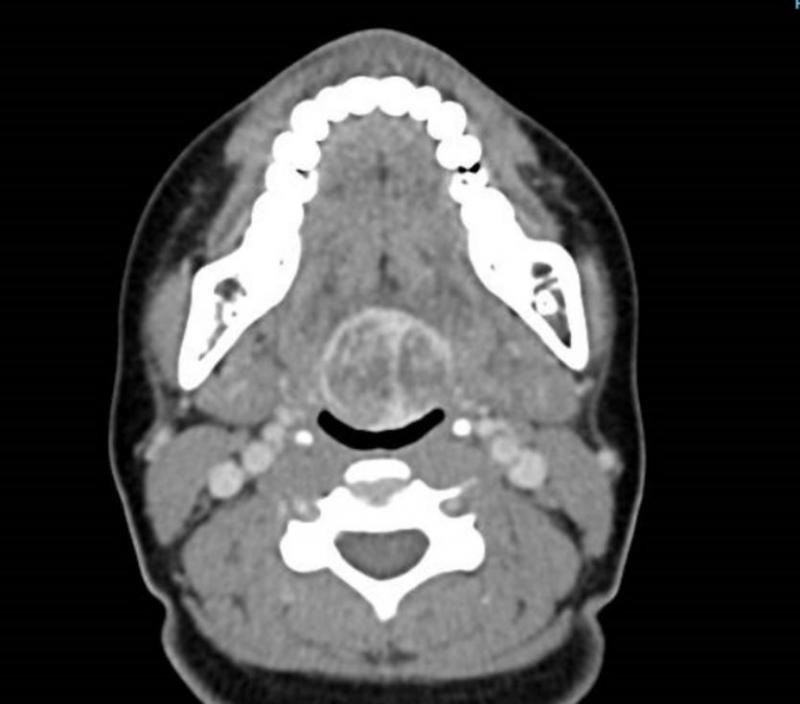

·甲状腺隐藏在舌根里:甲状腺在发育过程中未下降到颈项前的正常位置,而出现于其他部位,称为异位甲状腺。这是一种罕见的胚胎发育异常疾病。甲状腺最常隐藏的部位是舌根中线区,女性多于男性。

如果男女到了十七八岁,甲状腺还未下降到颈项前,睡觉时就容易引发窒息。治疗法是割除甲状腺,病人过后可口服甲状腺素片发挥甲状腺功能。